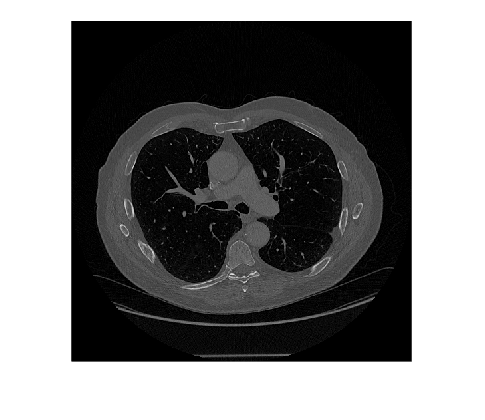

Extract the voxel data from the volume, which will be passed to the pretrained network. Display a slice of the rotated volume to check the updated orientation.

V = medVolReoriented.Voxels; imshow(V(:,:,150),[])